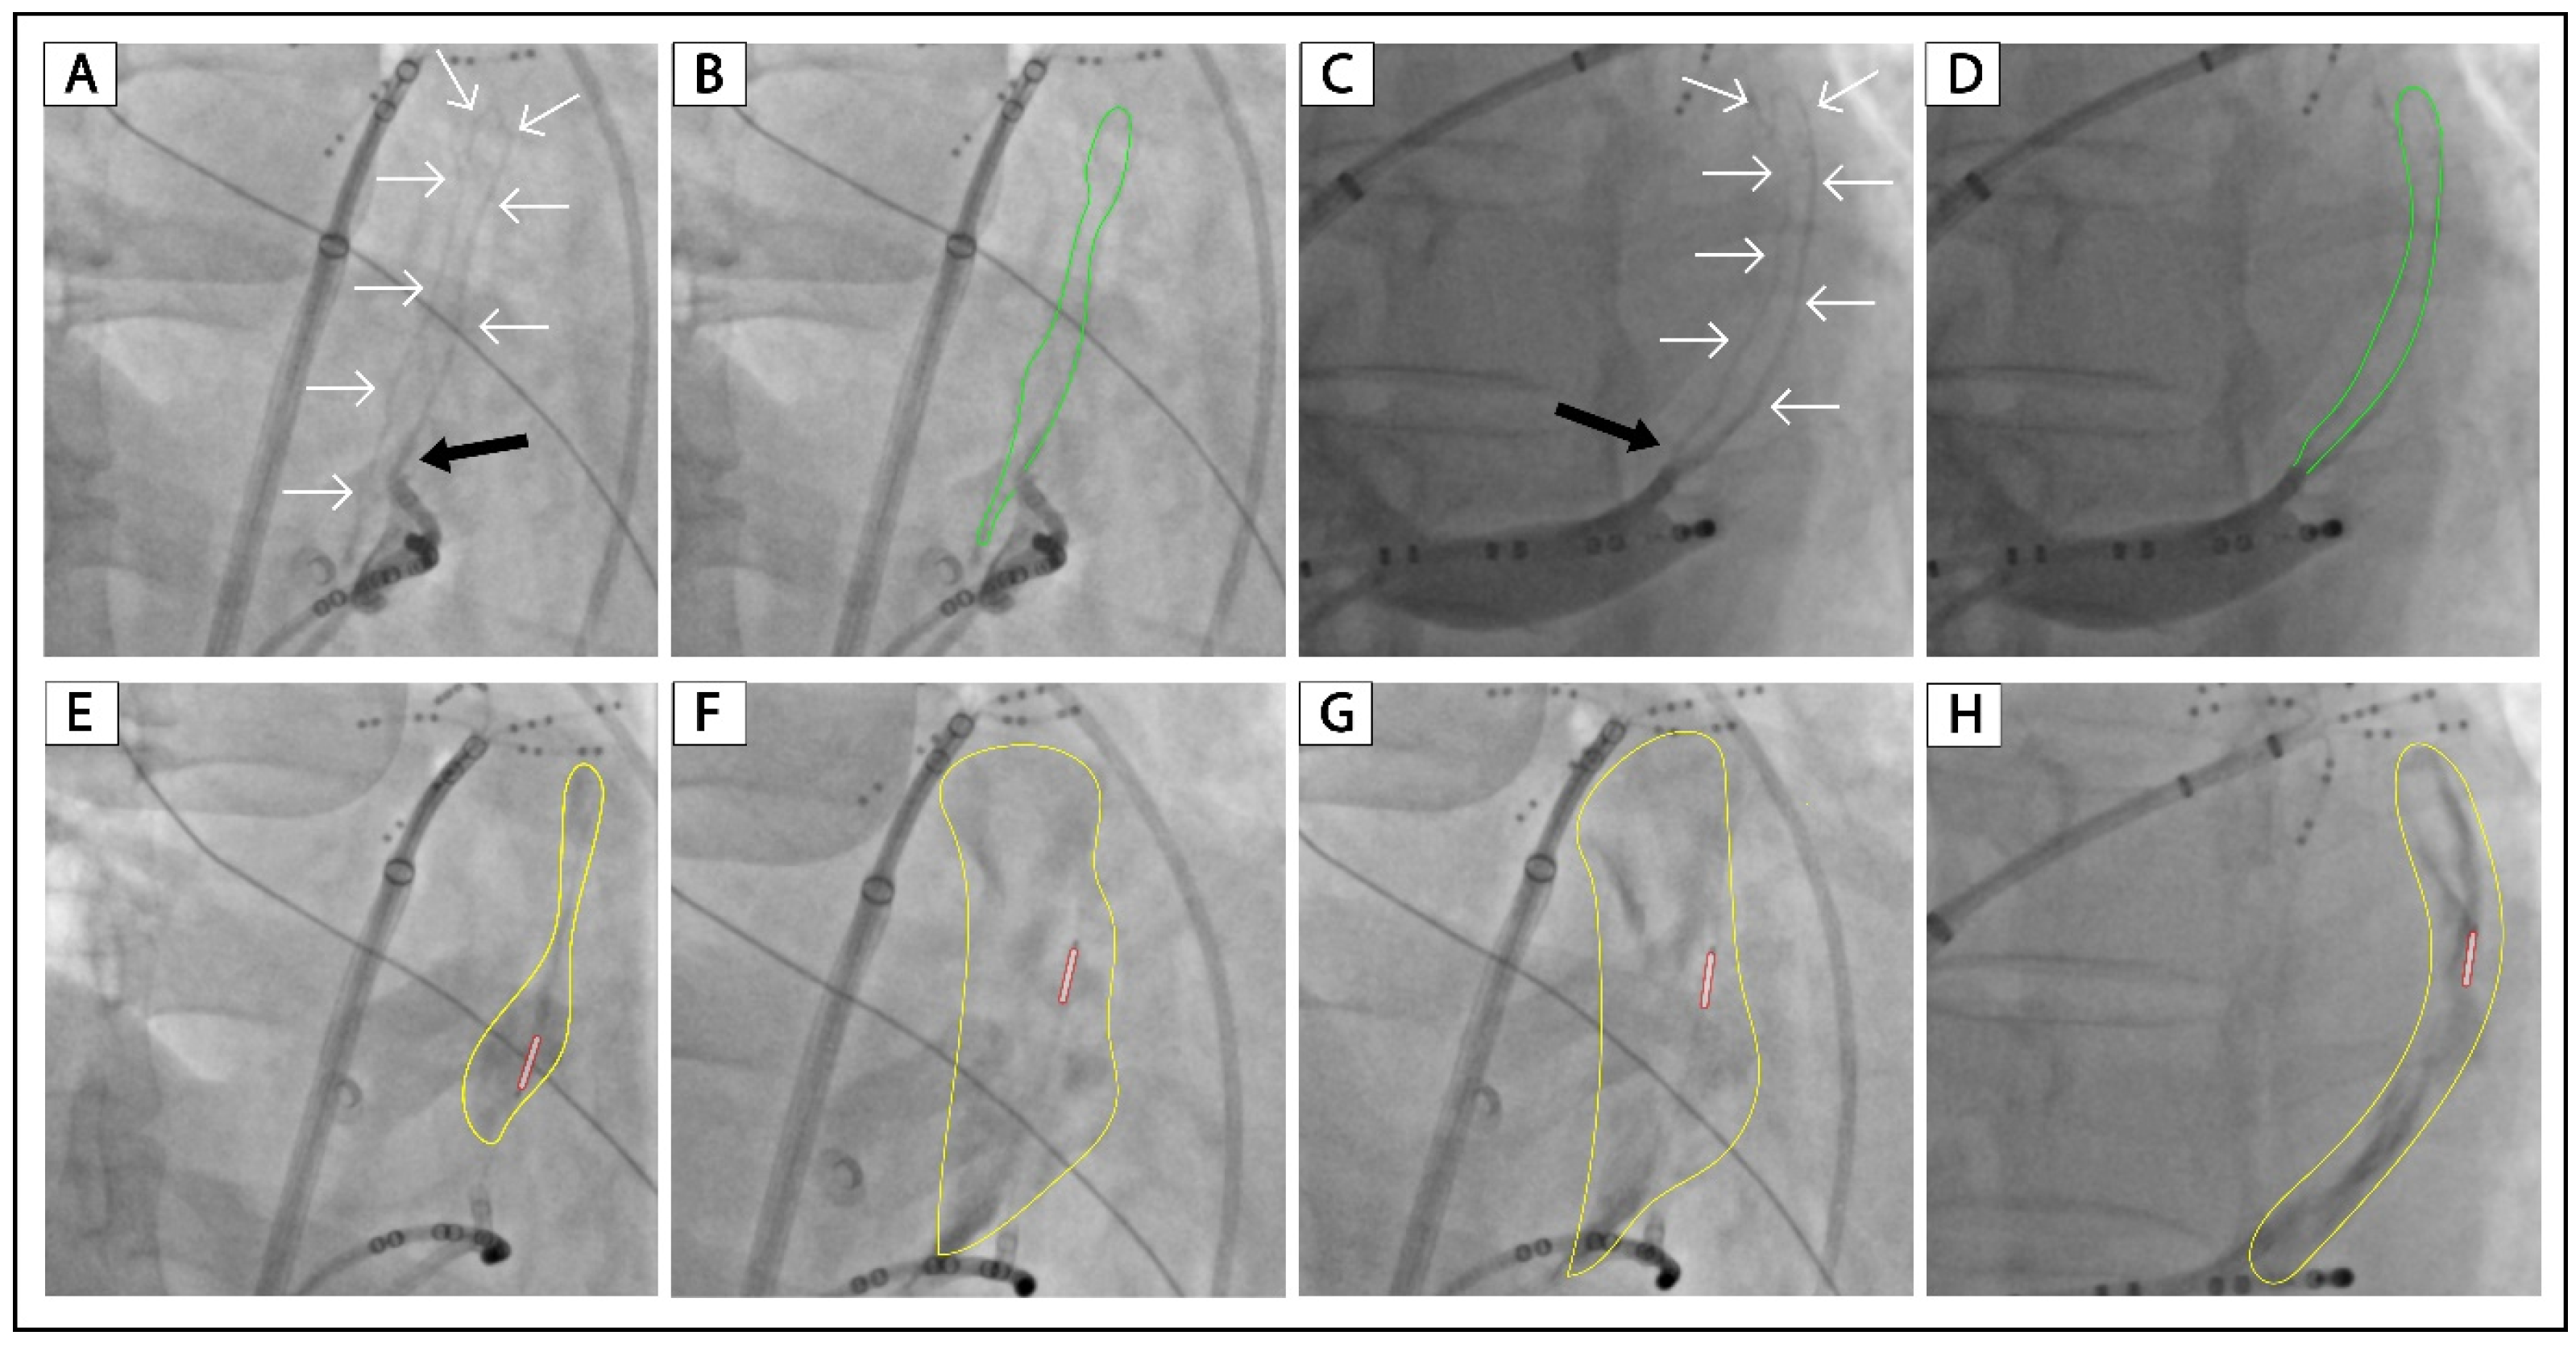

3.3. Examples of VOM Collateralization without Ethanol Infusion Attempt

3.4. Examples of VOM Collateralization with Successful Ethanol Infusion